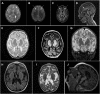

There are recent reports of associations of variants in the HPDL gene with a hereditary neurological disease that presents with a wide spectrum of clinical severity, ranging from severe neonatal encephalopathy with no psychomotor development to adolescent-onset uncomplicated spastic paraplegia. Here, we report two probands from unrelated families presenting with severe and intermediate variations of the clinical course. A homozygous variant in the HPDL gene was detected in each proband; however, there was no known parental consanguinity. We also highlight reductions in citrate synthase and mitochondrial complex I activity detected in both probands in different tissues, reflecting the previously proposed mitochondrial nature of disease pathogenesis associated with HPDL mutations. Further, we speculate on the functional consequences of the detected variants, although the function and substrate of the HPDL enzyme are currently unknown.